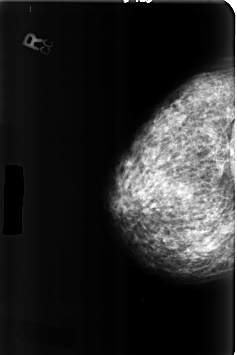

B_3357_1.LEFT_MLO

LEFT_CC LINES 4664 PIXELS_PER_LINE 3096 BITS_PER_PIXEL 12 RESOLUTION 50 OVERLAY

LEFT_MLO LINES 4640 PIXELS_PER_LINE 3080 BITS_PER_PIXEL 12 RESOLUTION 50 OVERLAY